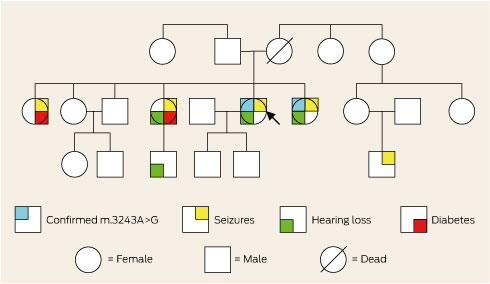

The patient’s family was of Aboriginal Australian descent and she was not aware of any European ancestry. Further inquiry revealed a family history of deafness, diabetes and epilepsy (Box 2). Consequently, the family were offered genetic counselling. A literature review prompted initiation of arginine and coenzyme Q10 therapy.3 Twelve months later, she had good seizure control and had not been re-hospitalised.